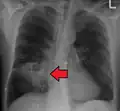

Lung abscesses are often on one side and single involving posterior segments of the upper lobes and the apical segments of the lower lobes as these areas are gravity dependent when lying down. Presence of air-fluid levels implies rupture into the bronchial tree or rarely growth of gas forming organism.

Pulmonary abscess on CT scan -

Pulmonary abscess on CXR -